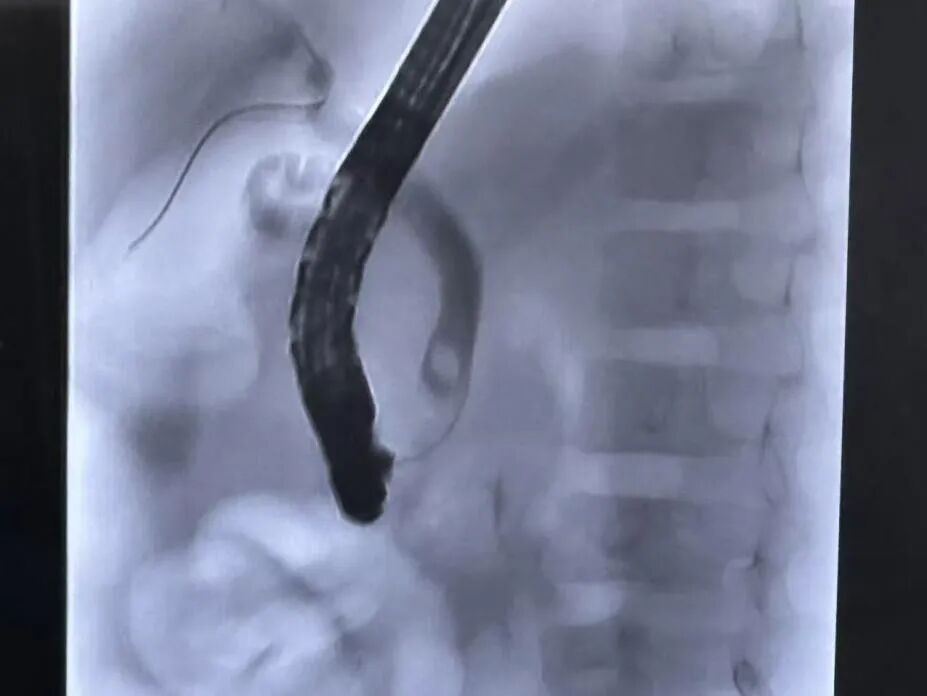

当天中午,在医生熟练的操作下,十二指肠镜顺利到达十二指肠乳头处,发现十二指肠乳头肿胀明显,通过一系列复杂的内镜下操作,一枚直径近1cm的结石被顺利取出,大量混着胆泥的浓稠胆汁不停涌出,为了更快排出这些积聚的胆汁,同时还留置了鼻胆管,整个手术操作时间仅1个小时。术后第一天患儿黄疸指数及胰腺炎相关指标复查均显著下降,症状缓解,第二天便逐步开放了饮食,病情快速恢复。